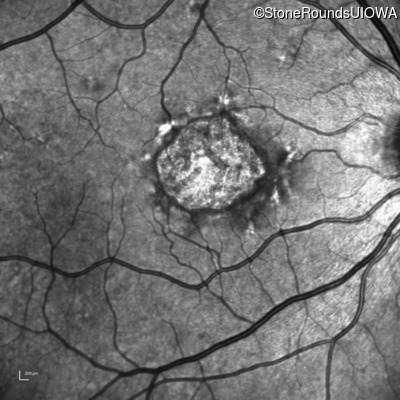

Pattern Dystrophy (IIC)

Age at visit: 51 years

This 51 year old woman first noticed some metamorphopsia in her left eye in her early 30's.

Pattern Dystrophy PRPH2 IVS2+3 A>T   AD